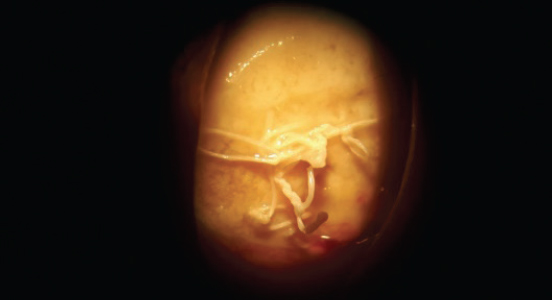

Наличие шовного материала выявлено у 5 оперированных пациентов (рис. 3, 4), у 3 пациентов были неоднократные попытки наложения швов для закрытия дефекта конъюнктивы. У 21 осмотренного пациента поверхность культи была покрыта конъюнктивой, у 9 — выявлены её дефекты (рис. 5). У 6 больных в сводах отмечены грануляционные изменения и рубцовые деформации слизистой оболочки культи и сводов (рис. 6).

Рис. 3. Пациент, 45 лет. Узлы нерассасывающегося шовного материала на передней поверхности опорной культи

Fig. 3. Patient, 45 y. o. Knots of non-absorbable material on the front surface of the stump

Рис. 4. Шовный материал на передней поверхности культи. Обнажение имплантата (фото-щелевая лампа)

Fig. 4. Suture material on the stump, implant exposure (photo slit lamp)